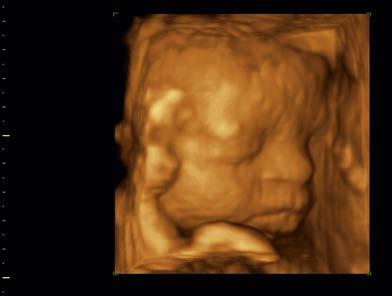

For decades, sonography was limited to 2D cross-sectional scans (or “slices”) through the anatomy. Today, 2D imaging,

while still being used extensively, has been extended to 3D scanning and imaging, also called volume imaging. This method requires scanning the ultrasound through many adjacent 2D tissue cross-sections to compose a 3D volume of echo information similar to a loaf of sliced bread (Figure 1-11). This 3D volume of echoes can then be processed and accessed to present 2D or 3D images of the anatomy.

FIGURE 1-11 Three-dimensional (volume) sonographic images. A, Three-dimensional echo data acquired by obtaining many two-dimensional sections of echo information (colored slices) from the imaged anatomy, forms a three-dimensional volume of stored echo information (blue box). B, Cardiac four-chamber view. C, Fetal head.